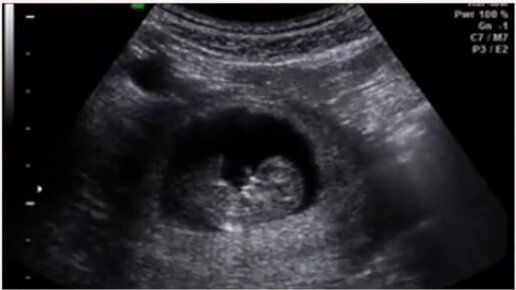

УЗИ на 10 неделе беременности